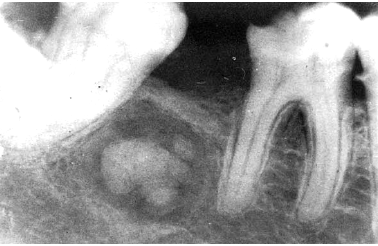

aneurysmal bone cyst

not a true cyst, caused by increased venous pressure with resultant dilation and rupture of the local vascular network

“blood soaked sponge” as surgical finding

arising in a pre-existing bone lesion

may cause pain and swelling

large unilocular or multilocular radiolucency